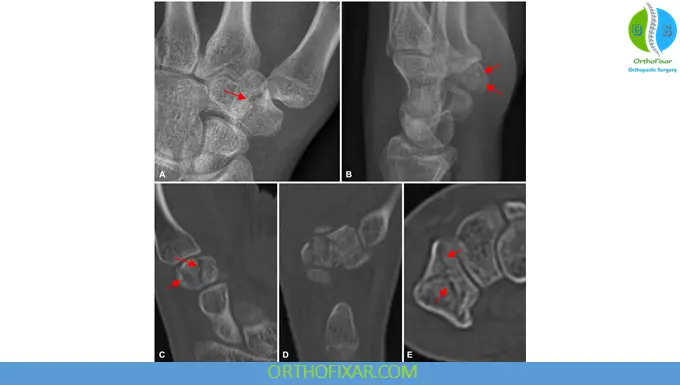

Diagnostic Evaluation

Radiographic Imaging

Standard imaging includes:

- Posteroanterior (PA) view

- Lateral view

- Robert view: A specialized true PA projection of the thumb CMC joint with the hand in maximum pronation, which minimizes overlap of the first metacarpal base.

Additional imaging:

- Carpal tunnel view: Useful for detecting dorsal ridge fractures

- CT scan: Highly sensitive for occult fractures and detailed assessment of articular involvement